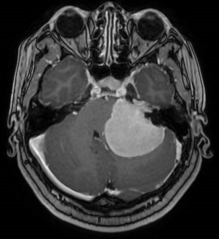

听神经瘤术前核磁 术后CT